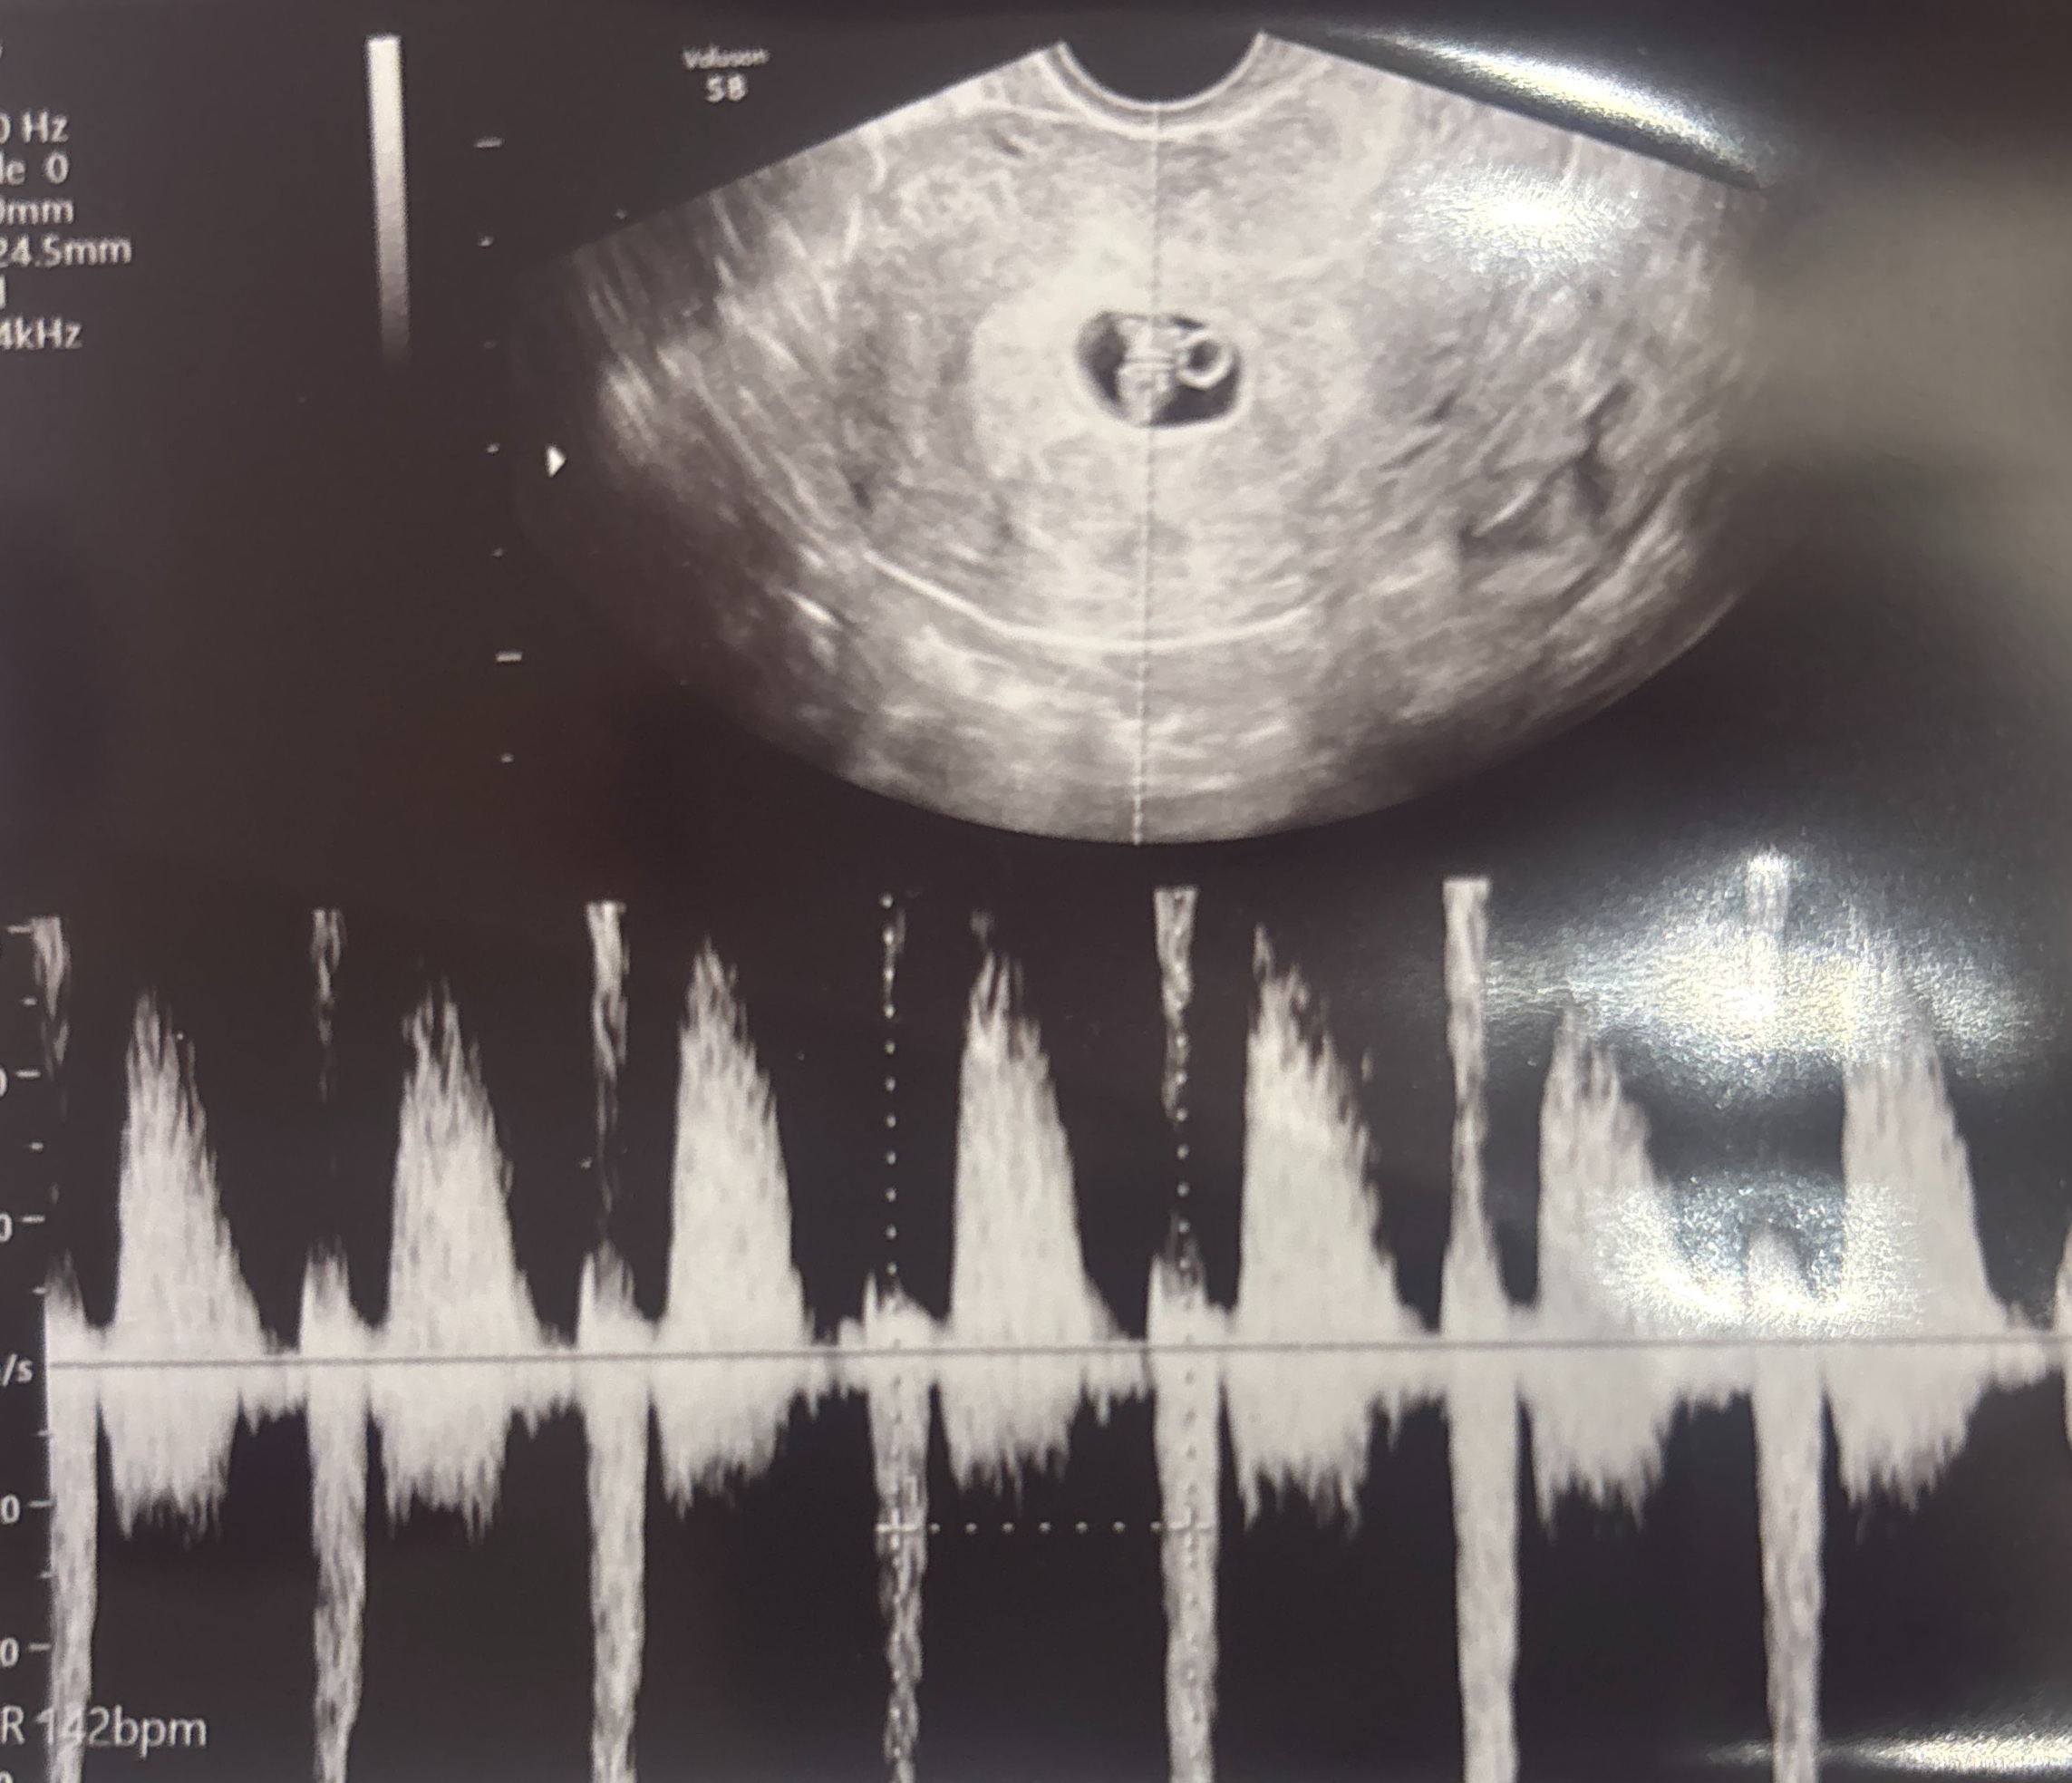

| 가슴 떨리는 임신 이야기를 공유해 주세요. | 나이와 낮은 확률로 걱정이 많았던 인공수정이었지만, 첫 시도에서 화학적 유산을 겪은 뒤 다시 도전했던 두 번째 시도에서 아기가 찾아와 주었습니다. 예상하지 못했던 기적 같은 순간이었습니다. |

| 치료 도중 느꼈던 가장 기뻤던 순간과 절망적인 것들은 무엇인가요? 잊지 못할 경험이 있나요? | 첫 인공수정에서 피검사 수치가 더블링되지 않아 화학적 유산이 되었을 때는 정말 절망적이었습니다. 하지만 바로 다음 시도에서 임신에 성공했을 때는 그만큼 더 큰 기쁨을 느낄 수 있었습니다. |